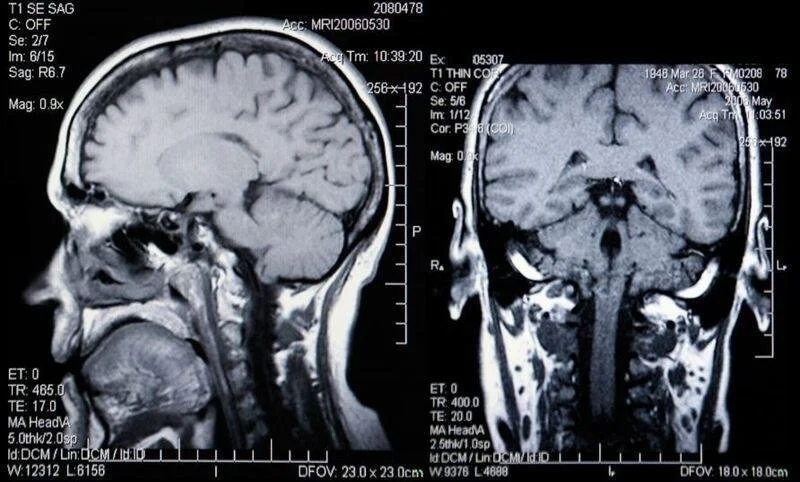

Lobotomy is a surgical procedure developed almost a century ago to treat severe mental health conditions. The procedure has varied throughout history but usually involves inserting a sharp instrument into the brain to sever certain neural connections.

Prefrontal lobotomy: The surgeon drills holes in either the side or top of the skull and then uses an ice pick-like surgical instrument called a leucotome to manually sever connections in the brain's prefrontal cortex which controls higher cognitive functions like memory, emotions, and problem-solving skills.

Transorbital lobotomy: This procedure works the same way as a prefrontal lobotomy, but the surgeon accesses the person’s brain through their eye sockets.